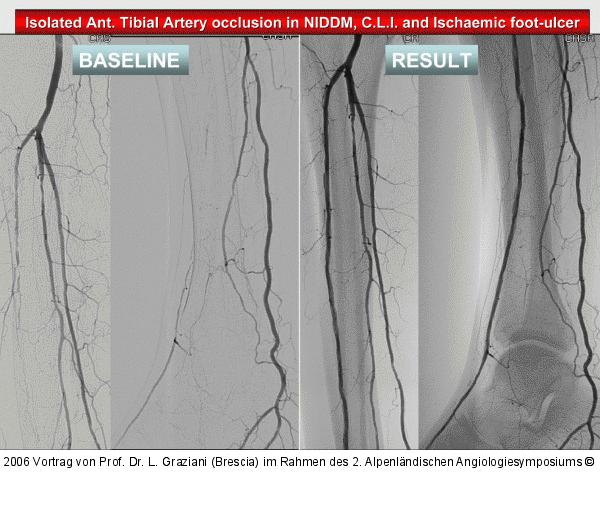

Vortrag von Prof. Dr. L. Graziani (Brescia) im Rahmen des 2. Alpenländischen Angiologiesymposiums

PTA of the foot arteries in diabetics: Extremities Extreme Angioplasty

Abbildung 48: Tibialarterie